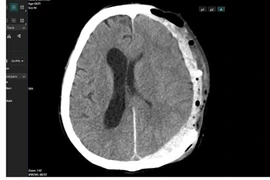

(khoahocdoisong.vn) - Chấn thương sọ não nặng được điều trị bằng phẫu thuật, hồi sức hoặc phối hợp. Kết quả hồi sức và điều trị bệnh nhân chấn thương sọ não nặng phụ thuộc vào nhiều yếu tố như tuổi, tình trạng bệnh nhân, tổn thương tại não, tổn thương phối hợp, thời điểm điều trị.

(khoahocdoisong.vn) - Chấn thương sọ não thường bắt nguồn từ các loại chấn thương về não bao gồm chảy máu, chấn động mạnh, rung động não hoặc não bị bầm.